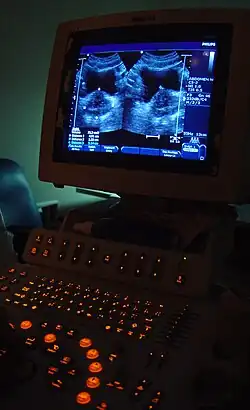

Some forms of medical imaging exist to visualise the bladder. A bladder ultrasound may be conducted to view how much urine is within the bladder, indicating urinary retention. A urinary tract ultrasound, conducted by a more trained operator, may be conducted to view whether there are stones, tumours or sites of obstruction within the bladder and urinary tract. A CT scan may also be ordered.